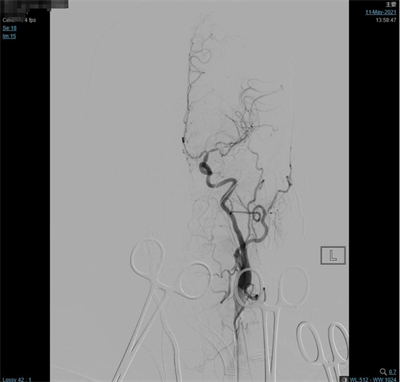

脑动脉造影(外院,2021-5-10):双侧大脑中动脉分叉多发动脉瘤。

夹闭前造影

夹闭后造影